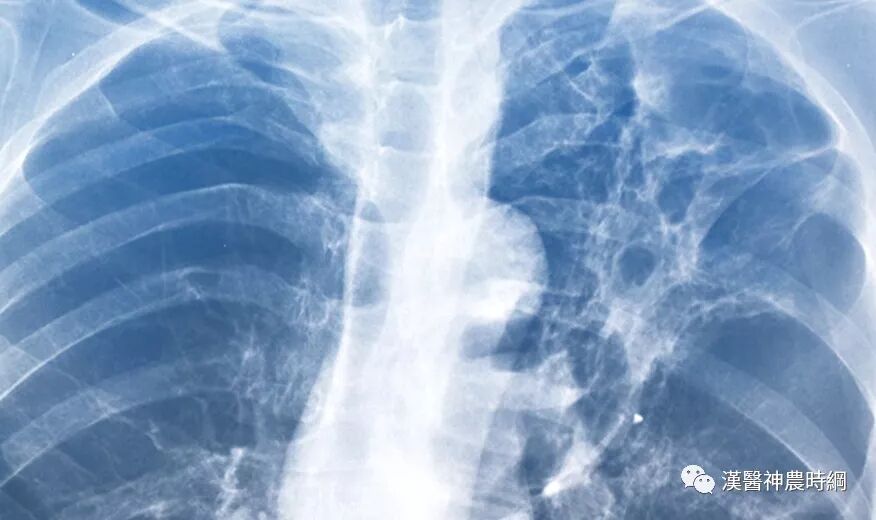

基于以上病理变化,临床上多表现为进行性呼吸困难或伴有刺激性干咳,胸部X线显示两中下肺野网状阴影,肺功能为限制性通气功能障碍。病情呈持续性进展,最终因呼吸衰竭而死亡。

早期虽有呼吸困难,但X线胸片可能基本正常;中后期出现两肺中下野弥散性网状或结节状阴影,偶见胸膜腔积液,增厚或钙化。肺组织纤维化的严重后果,导致正常肺组织结构改变,功能丧失。就是大量没有气体交换功能的纤维化组织代替肺泡,导致氧不能进入血液。患者呼吸不畅,缺氧、酸中毒、丧失劳动力、靠呼吸机生存,最后衰竭、死亡。